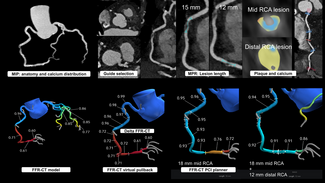

Bilateral femoral arterial access was obtained using 8 Fr 45 cm long sheaths. The RCA was initially engaged with an 8 Fr JR4 guide that provided poor to moderate support. The left main was engaged with a XB 3.5 guide. Coronary angiography using dual injection demonstrated marked calcification in the RCA with a 30 mm mid level occlusion (Figure 1A). The mid RCA filled via collaterals from the LAD and the circumflex and reconstitution of the mid RCA occurred at the site of origin of a large acute marginal branch.

We initially attempted to cross antegradely using several wires including the Fielder XT and Confianza Pro 12 wire (Asahi Intecc) through a 1.5 mm x 8 mm over-the-wire balloon without success. The JR4 guide did not provide enough support and was changed for an AL1 guide that did not fit well and provided marginally better support. We tried to cross with a CrossBoss catheter (Bridgepoint Medical) unsuccessfully, followed by a Finecross (Terumo) with Pilot 200 (Abbott Vascular) and Confianza Pro 12 (Asahi Intecc) wires, also unsuccessfully. We changed the guide to an AL 0.75 but were still unable to cross with various wires including Pilot 200, Progress 200, and Pilot 150 (Abbott Vascular).

We attempted to wire retrogradely, but were unable to cross through septal collaterals in part due to a previously placed LAD stent. We engaged the RCA with a 7 Fr Champ 2 guide and wired into the acute marginal distal to the CTO using a Pilot 150 wire (Abbott Vascular) through a Finecross microcatheter (Terumo) (Figure 1B). We encountered severe difficulty crossing the CTO with a balloon. We inflated several 1.5 mm balloons into the lesion but were unsuccessful in crossing. We used a 7 Fr Guideliner catheter (Vascular Solutions) to deeply engage the RCA and were then able to cross with a 1.5 mm balloon. We predilated several times with 1.5 mm and 2.0 mm balloons, restoring antegrade flow through the RCA CTO (Figure 1C).

We could not wire antegradely into the mid RCA in spite of using multiple wires, as there was an acute bend at the origin of the acute marginal branch. We eventually used a "hairpin wire" technique, in which a Whisper wire (Abbott Vascular) was bent approximately 3 cm from its tip, advanced into the acute marginal branch, and pulled back (Figures 1D and 1E). We then attempted to advance a balloon into the distal RCA, but were not successful and in the process, the guidewire and guide catheter position were lost.